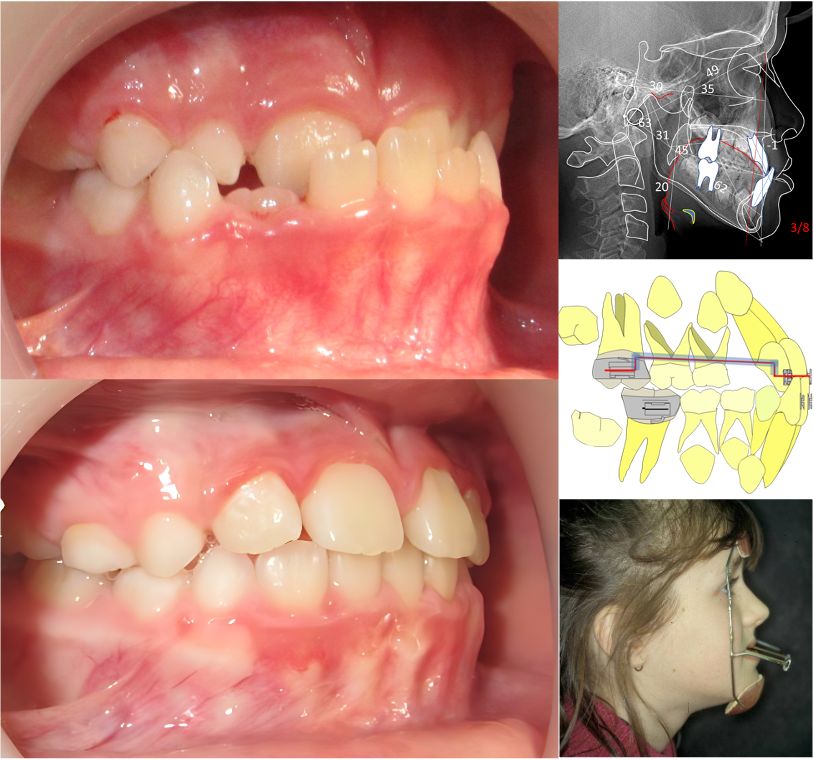

Stage 5: Les traitements fonctionnels et orthopédiques des classes II (exclusivement en webinaire)

Après ce stage vous serez capable de :

1. Dépister et diagnostiquer les malocclusions de classe II

2. Choisir le bon moyen thérapeutique selon le diagnostic différentiel de chaque cas

3. Mettre en application des propulseurs : PUL, EF, Elastodontie….

4. Connaitre les complications d’une prise en charge tardive d’un cas de classe II orthopédique

Stage 9: Les stratégies thérapeutiques des classes III

1. Dépister et diagnostiquer les malocclusions de classe III

3. Intervenir précocement pour éviter l’installation et l’aggravation d’une Classe III

4. Mettre en place une thérapeutique orthopédique et orthodontique appropriée en fonction de l’âge du patient

5. Séquences thérapeutiques de traitement de Classe III orthodontique